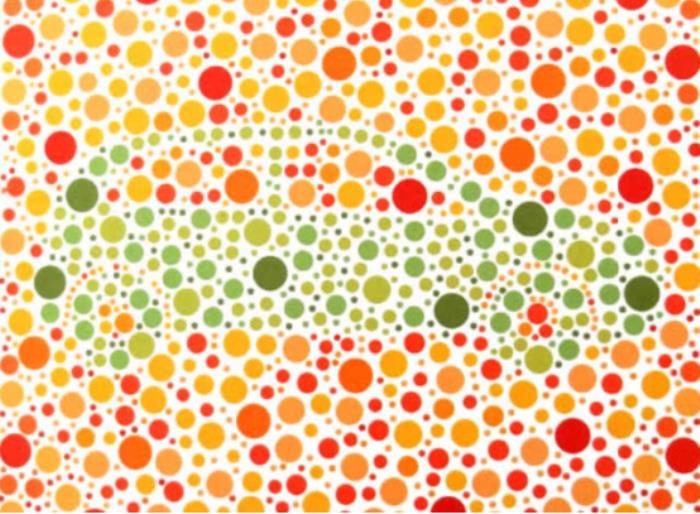

·形状图1

结果:正常看到的是正方形、三角形

·形状图2

结果:正常看到的是一大一小,两个圆形

·形状图3

结果:正常看到的是一个圆形

·形状图4

结果:正常看到的是五角星(可以尝试离手机远一点看)

·动物图1

结果:正常看到的是金鱼

·动物图2

结果:正常看到的是白色鸭子和红色兔子,红绿色盲只能看到鸭子

·动物图3

结果:正常看到的是狗

·动物图4

结果:正常看到的是小鸟

终极测试!!下面这张图你看到了什么数字?

结果:

左图:全色弱者及正常者读不出来,红绿色盲者及红绿色弱者大多能看到5

右图:正常者及全色弱者大多找不到,红绿色盲者及红绿色弱者容易找到